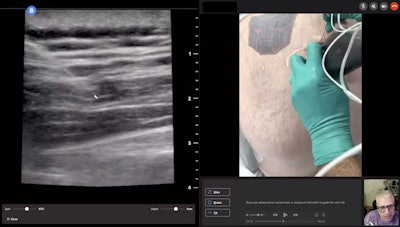

Ruma sees specific benefits of teleultrasound and Collaboration Live software for perinatal care, permitting him to operate the scanner, drawing arrows on the remote screen and directing patients to what he is looking at. He can freeze images and also look at calculations, as well as share his screen and other information over the remote ultrasound scanner.

"All of those capabilities truly enhance the experience for me and for the sonographer and for the patient. It's exactly as if I walked into a room and talked to the patient," Ruma said. "Physically, I typically go through pictures on the ultrasound machine. I typically hit the trending graphs, show them things on the ultrasound system. I'm able to do that and operate that remotely from wherever I'm at in the world."

"What is really cool with teleguidance is that I can actually say, 'Here is what you are doing wrong with your hand position,' " Weimersheimer explained. "It is as if I was at the bedside, but I am five or six hours away."